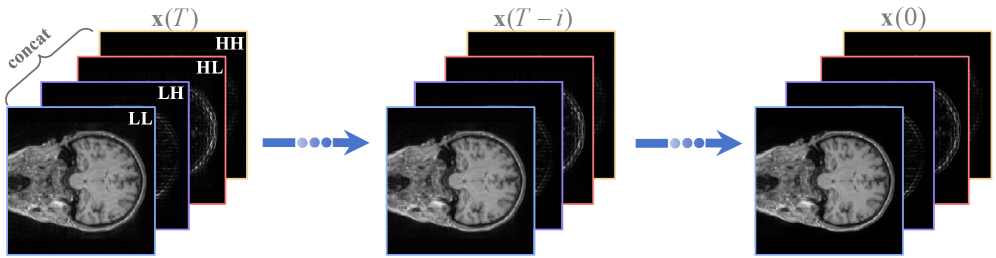

Wavelet transform is a classic image compression technique used to separate different frequency components from the original image. Among them, Haar wavelet transform is widely used in practical applications due to its simplicity [31]. It involves operations: discrete wavelet transform (DWT) and the inverse discrete wavelet transform (IDWT).

We decompose the input image into four wavelet subbands: LL, HL, LH, and HH via the DWT. As shown in Fig. 2, the wavelet domain components are fed into the network, the score function is obtained in the wavelet domain, and then converted to the image domain for continuous iteration. The above process is equivalent to performing a diffusion process in the wavelet domain, as shown in Fig 3. Benefiting from the reduction of input image resolution, the testing time of the proposed model is reduced.